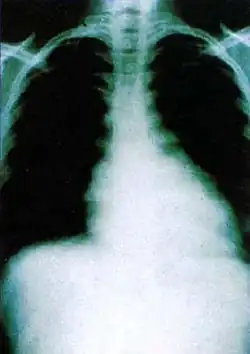

Czynnikiem determinującym przeżycie chorych z trypanosomiazą jest przede wszystkim wydolność krążenia warunkowana przez zajęcie mięśnia sercowego przez świdrowce. W 2006 roku opracowano i opublikowano w „New England Journal of Medicine” kryteria rokowania w chorobie Chagasa mięśnia sercowego[57]. Na podstawie badań obejmujących grupę ponad 500 pacjentów określono czynniki rokownicze: kliniczną ocenę wydolności krążenia (stopień w skali NYHA), ocenę radiologiczną sylwetki serca, ocenę EKG, wynik badania echokardiograficznego i holterowskiego.